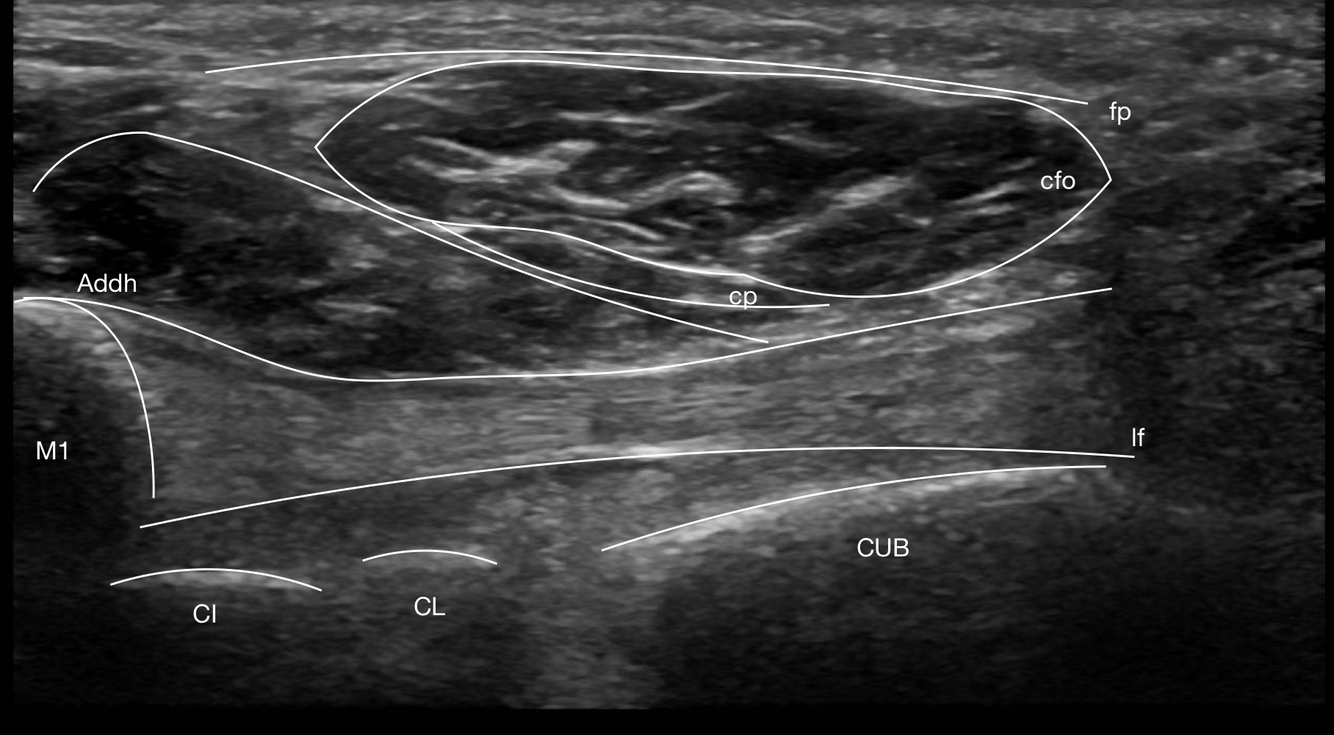

Identifier les structures suivantes

- Tibial post

- LFO

- Nerf tibial

Identifier les 6 structures situées en médial de la cheville